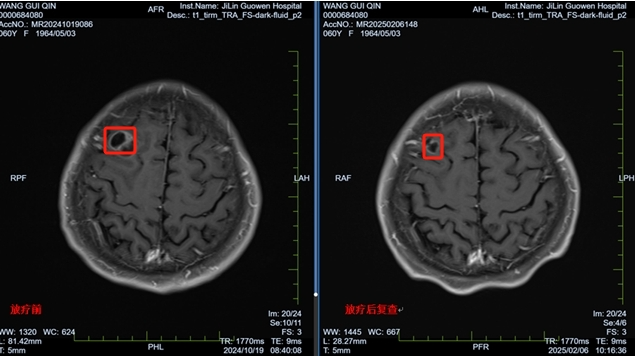

經(jīng)過一個療程的放療,王阿姨的頭痛、惡心等癥狀明顯緩解,精神狀態(tài)好轉(zhuǎn)。本次復(fù)查結(jié)果顯示,腦部腫瘤明顯縮小,病情得到有效控制。王阿姨重新燃起了對生活的希望,樂觀面對未來。